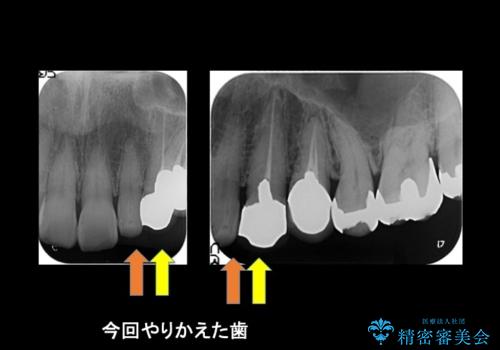

被せ物だけやりかえており、患者様のご希望もあり、根の治療や土台(コア)のやりかえは行なっていません。

- 左上の前歯が小さく左右対称ではないのと、保険の前歯の被せ物のやりかえを希望して来院。

小さい前歯は、反対側と合わせた形にしました。